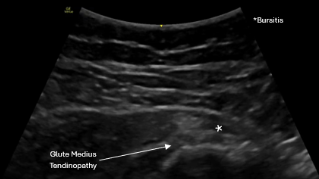

The Hip Is a Complex Joint

Hip pain can originate from:

- Gluteus medius or minimus tendons

- Greater trochanteric bursa

- Rectus femoris tendon

- Hip joint (labrum or osteoarthritis)

- Proximal hamstring tendon

- IT band irritation

- Deep posterior hip structures

Symptoms overlap significantly.

Without imaging, lateral hip pain is often labeled “bursitis,” anterior pain is dismissed as tight hip flexors, and posterior pain is misattributed to the low back.

Ultrasound helps differentiate exactly where the pain and dysfunction are coming from — which completely changes treatment.